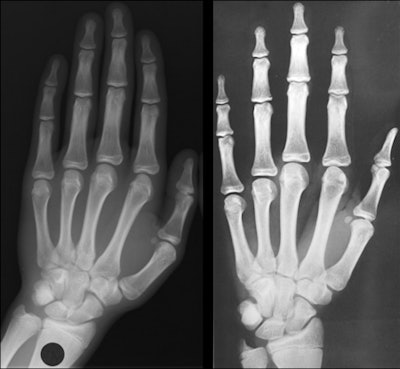

The two most widely used systems are the Greulich and Pyle Atlas (GP) and the Tanner Whitehouse (TW) methods. Published in 1959, GP is the most widely used. It is based on hand x-rays from 1,000 Americans of northern European descent living in Ohio, between 0 years and 18 years in, which were taken from the Brush Foundation longitudinal study between 1931 and 1942 and compiled into an atlas. To help determine bone age, plain x-rays of the left hand and wrist can be compared with reference atlas images for each age category and both sexes.

Evaluation is based on the existence and morphology of the epiphyses of the metacarpals and the phalanges and their fusion, the carpal bones, and the inferior epiphyseal points of the ulna and radius. While it is simple, with low inter- and intraobserver differences, critics state that the method is based on an old study and is not representative of modern, multiethnic, taller, and heavier populations from various socioeconomic backgrounds.

The Tanner Whitehouse method, based on data compiled in 1962 from British children born between 1940 and 1955, involves the assignment of a score to each of the ossification centers, involving 20 bones, visible in the x-ray. The development of each bone within the hand/wrist complex is divided into a series of stages from A (initial radiological aspect) to H (final mature radiological aspect), when the bone has achieved full adult morphology. Each bone is assessed individually for stage, with each stage assigned a numeric score. All numeric scores are then added together to achieve a cumulative score, which is then related to a chronological age.

The method was updated with data from Scotland in 1975 (TW2) and then again in 2001 (TW3) with data from Europe, Argentina, Japan, and the U.S. However, it is time-consuming, difficult to learn, involves arbitrary assignment of scores to the degrees of maturity, and only gives a rough staging of ossification of the ulna and radius, according to Dedouit.